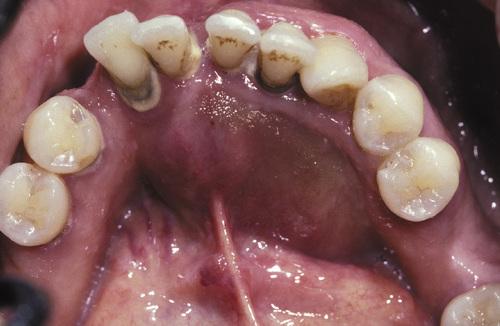

- Expansion of the posterior maxillary alveolus caused by a large pink lesion.

- Panoramic radiograph showing a large radiolucency with a small calcified structure is seen in the lower portion.

calcifying odontogenic cyst